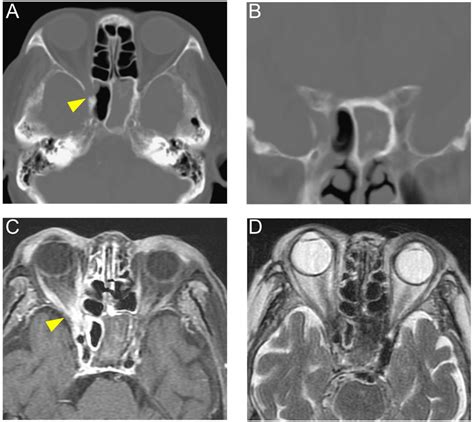

• Imaging Tests: CT scans or MRI scans to visualize the sphenoid sinuses and surrounding structures. These tests can help identify any abnormalities, blockages, or infections.